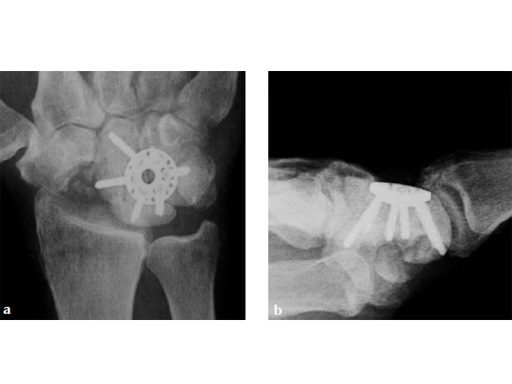

Case 1: SNAC wrist stage 3. Operative procedure and technical details.

Case provided by Ladislav Nagy, Zrich, Switzerland, and Fiesky Nez, Valencia, Venezuela.

Fig 1ab Preoperative x-rays. Notice the midcarpal joint destruction and the DISI deformity of the lunate.

Fig 2ab Dorsal intercalated segment instability correction and K-wire fixation.